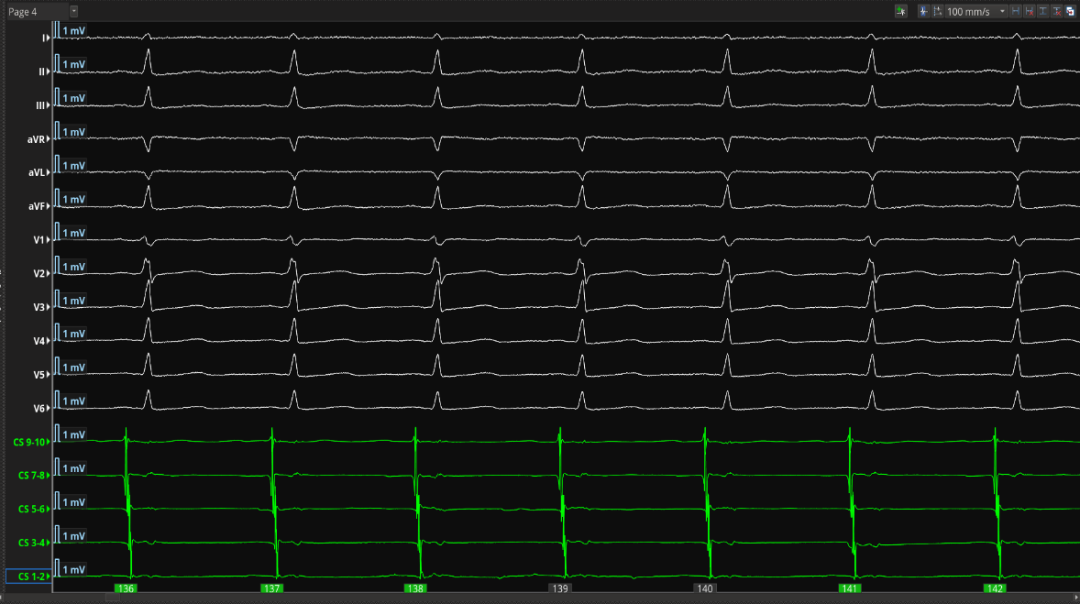

1.术中腔内及体表心电图

女,37岁,阵发性房颤,超声显示:LA内径34mm,左心耳未有明显血流淤滞。